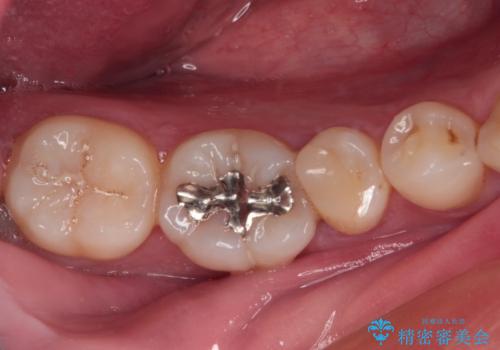

銀歯を白くして見た目を改善したい !

もげてしまった奥歯 オールセラミッククラウンでの補綴治療